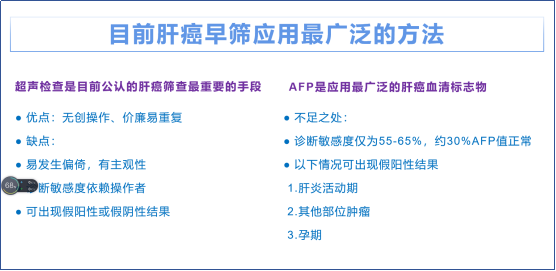

在全球范围内,每年新发肝细胞癌超过50万例,而且主要与慢性感染乙肝或丙肝病毒有关。尽管现有药物可以抑制乙肝病毒,丙肝已经能够被治愈,但乙肝和丙肝患者仍然有相对较高的风险发展为肝硬化,甚至肝癌。对这些慢性肝炎病毒感染者来说,有效预防病情发展的策略将大大改善他们的预后。